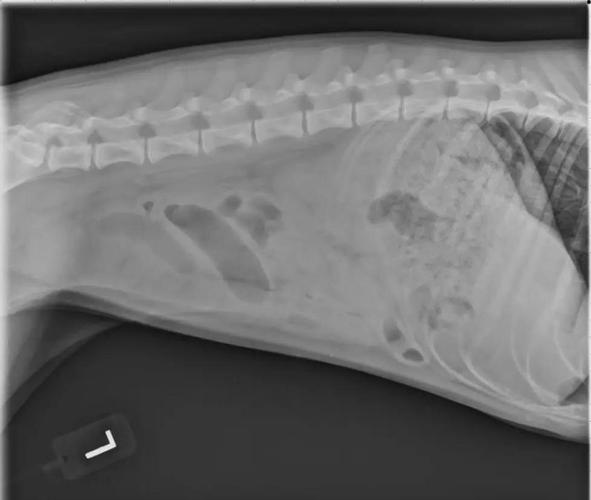

狗狗肠套叠的症状主要表现为剧烈呕吐、腹痛、血便以及腹部肿块。剧烈呕吐:患犬通常在进食后会立即呕吐,初期呕吐物中含有少量食物,随后呕吐物变为黏液性泡沫状物。腹痛:狗狗可能会表现出明显的腹痛症状,如弓背、呻吟或试图避免腹部被触摸。血便:随着病情的进展,患犬可能会出现血便,这是由于肠套叠导致的肠道出血。

狗狗肠套叠的症状主要有以下几点:剧烈呕吐:狗狗在吃完东西后会呕吐,呕吐物开始可能含有少量食物,之后可能变为粘液性泡沫状物。腹痛:狗狗会出现明显的腹痛症状,可能表现为腹部紧张、弓背等姿势。血便:狗狗的粪便中可能带有血液和黏膜。腹部肿块:在腹部可以触摸到肿块,这通常是套叠的肠管。

狗狗肠套叠的症状主要包括以下几点:突然发生剧烈的腹痛:病犬会表现出高度不安,甚至卧地打滚,使用镇静剂也难以使其安静。排便异常:病初可能会排稀粪,常混有多量粘液或血丝,严重时可排出黑红色稀便;后期可能会排粪停止。呕吐:当小肠发生套叠时,病犬常会出现呕吐症状。